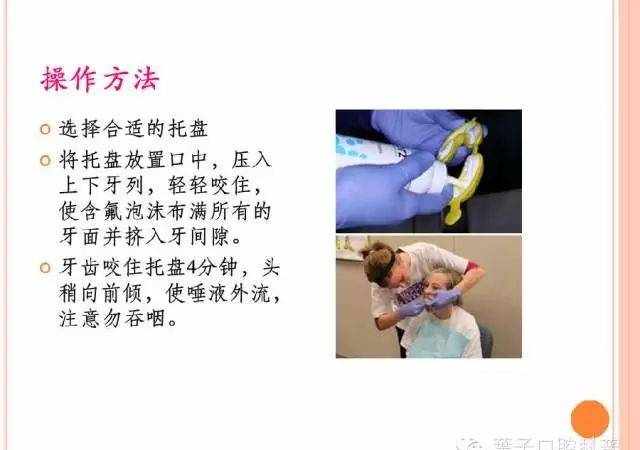

(1)氟凝胶

(2)氟化泡沫

(3)氟保护漆